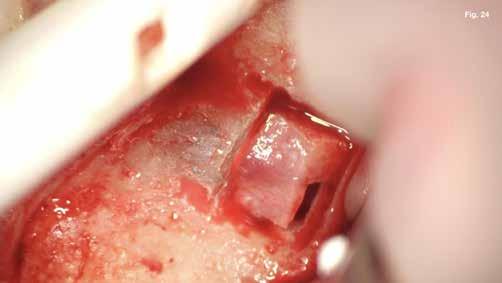

A szubmarginális teljes vastagságú lebenyt két felszabadító bemetszéssel végeztük egy 69-es számú, dupla lekerekített mikropengével (Swann–Morton) (6–7. ábra) A vestibularis csont ép volt, ezért csontablak-technikát alkalmaztunk és végeztünk (6–8. ábra) piezo készülékkel (Woodpecker DTE AI Surgery) és „US1, UC1” (Guilin Woodpecker Medical Instrument Co., LTD) hegyekkel. A blokkot az intraoperatív szakaszok alatt sóoldatban tartot-

tuk. Az apikális reszekciót (8. ábra) az „UC1” (Guilin Woodpecker Medical Instrument Co., LTD) segítségével végeztük el, és a gyökeret egy 3 mm-es „MM4” (Hu-Friedy Manufacturing Co. LLC) kerek tükörrel vizsgáltuk a VRF szempontjából (13. ábra). A gyökérvég polírozását (11. ábra) az „UL4” (Guilin Woodpecker Medical Instrument Co., LTD) segítségével végeztük. A csontos kripta küretizálása kézi küretezéssel történt, de a csontos kriptában lévő további hámbélés eltávolításával a gyógyulási folyamat felgyorsítása érdekében piezo „UL3” (Guilin Woodpecker Medical Instrument Co., LTD) piezo hegyet is használtunk (9–10. ábra). A három mm-es retropreparációt (14–17. ábra) a „JT2SA” hegy (B&L Biotech) segítségével végeztük el. A retropreparációt ismét ellenőriztük a guttapercha maradványok tekintetében, leöblítettük és papírhegyekkel meg-

szárítottuk (18–20. ábra), majd retropecsétet (21–23. ábra) készítettünk „Neo Mta plus” (Avalon Biomed). A csontos blokkot visszahelyeztük (24. ábra) az eredeti helyzetébe, és a „Jason membrán” (Botiss Biomaterials GmbH) reszorbálható kollagénmembránt használtunk a blokkablak lefedésére (25. ábra). A lágyrészek varrására (26. ábra) nem felszívódó 6,0 monofilamentumos varratokat használtunk (SMI), amelyeket az 5. napon eltávolítottunk (27. ábra).